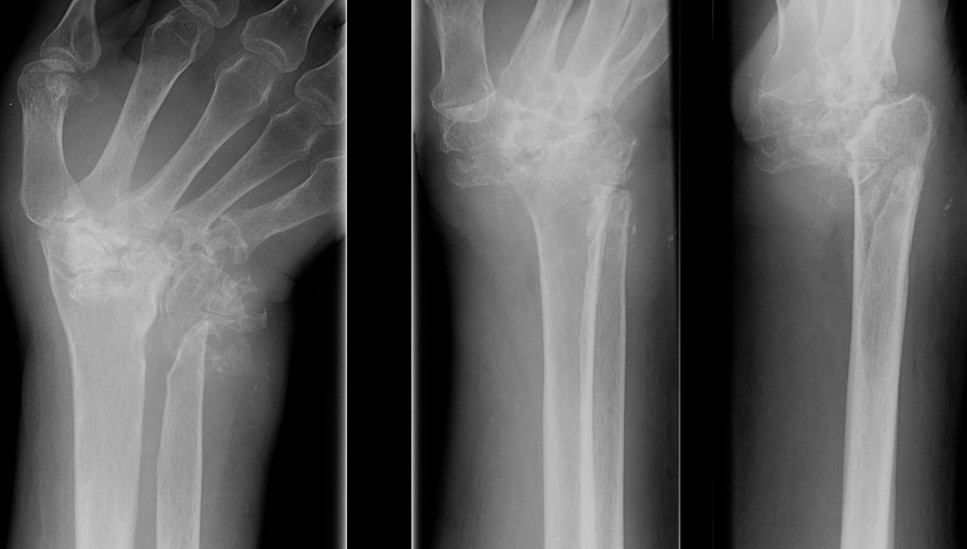

X-ray

Chronic Gouty Arthritis

- usually in feet in phalangeal heads

- characteristic periarticular bony defects

- punched out lytic appearance

- overhanging sclerotic margin (Martell's sign)

- also joint space narrowing & secondary OA

- no osteopenia compared with RA